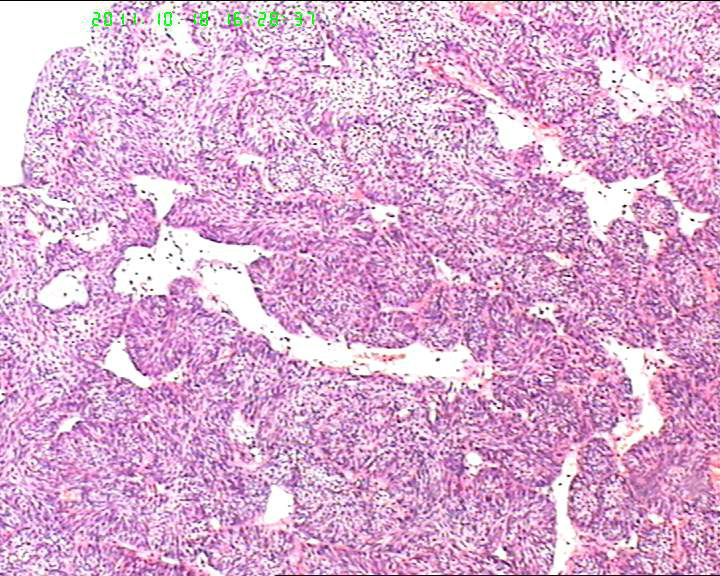

70岁女性体检发现膀胱肿物,是癌吗?

膀胱后壁一2*1cm大小肿物